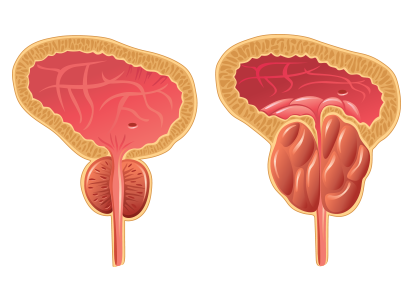

전립선비대증은 중년(50세 이후)의 남성에게 가장 대표적으로 나타나는 비뇨기 질환입니다. 방광 경부와 연결된 요도를 둘러싸는 전립선이 커지면서 요도를 압박하게 되므로 소변 줄기가 약해지고 배뇨 시간이 지연되며, 빈뇨, 야간뇨, 급박뇨, 잔뇨감 등의 다양한 배뇨 이상 증상이 나타납니다.

이러한 전립선비대증을 제대로 치료하지 않고 방치할 경우 이차적으로 방광의 변화를 유발하여 방광 기능 저하가 동반될 경우 소변을 보는 것이 더욱 어려워지게 되므로 조기 치료가 중요합니다.

비대해진 전립선 조직의 좌,우를 간단하게 묶어 고정함으로써 요도를 압박하는 전립선을 넓혀주는 방법입니다.

비대해진 전립선을 부분적으로 잘라내는 방법으로 효과는 좋은 편이지만 별도의 회복 시간이 필요합니다.